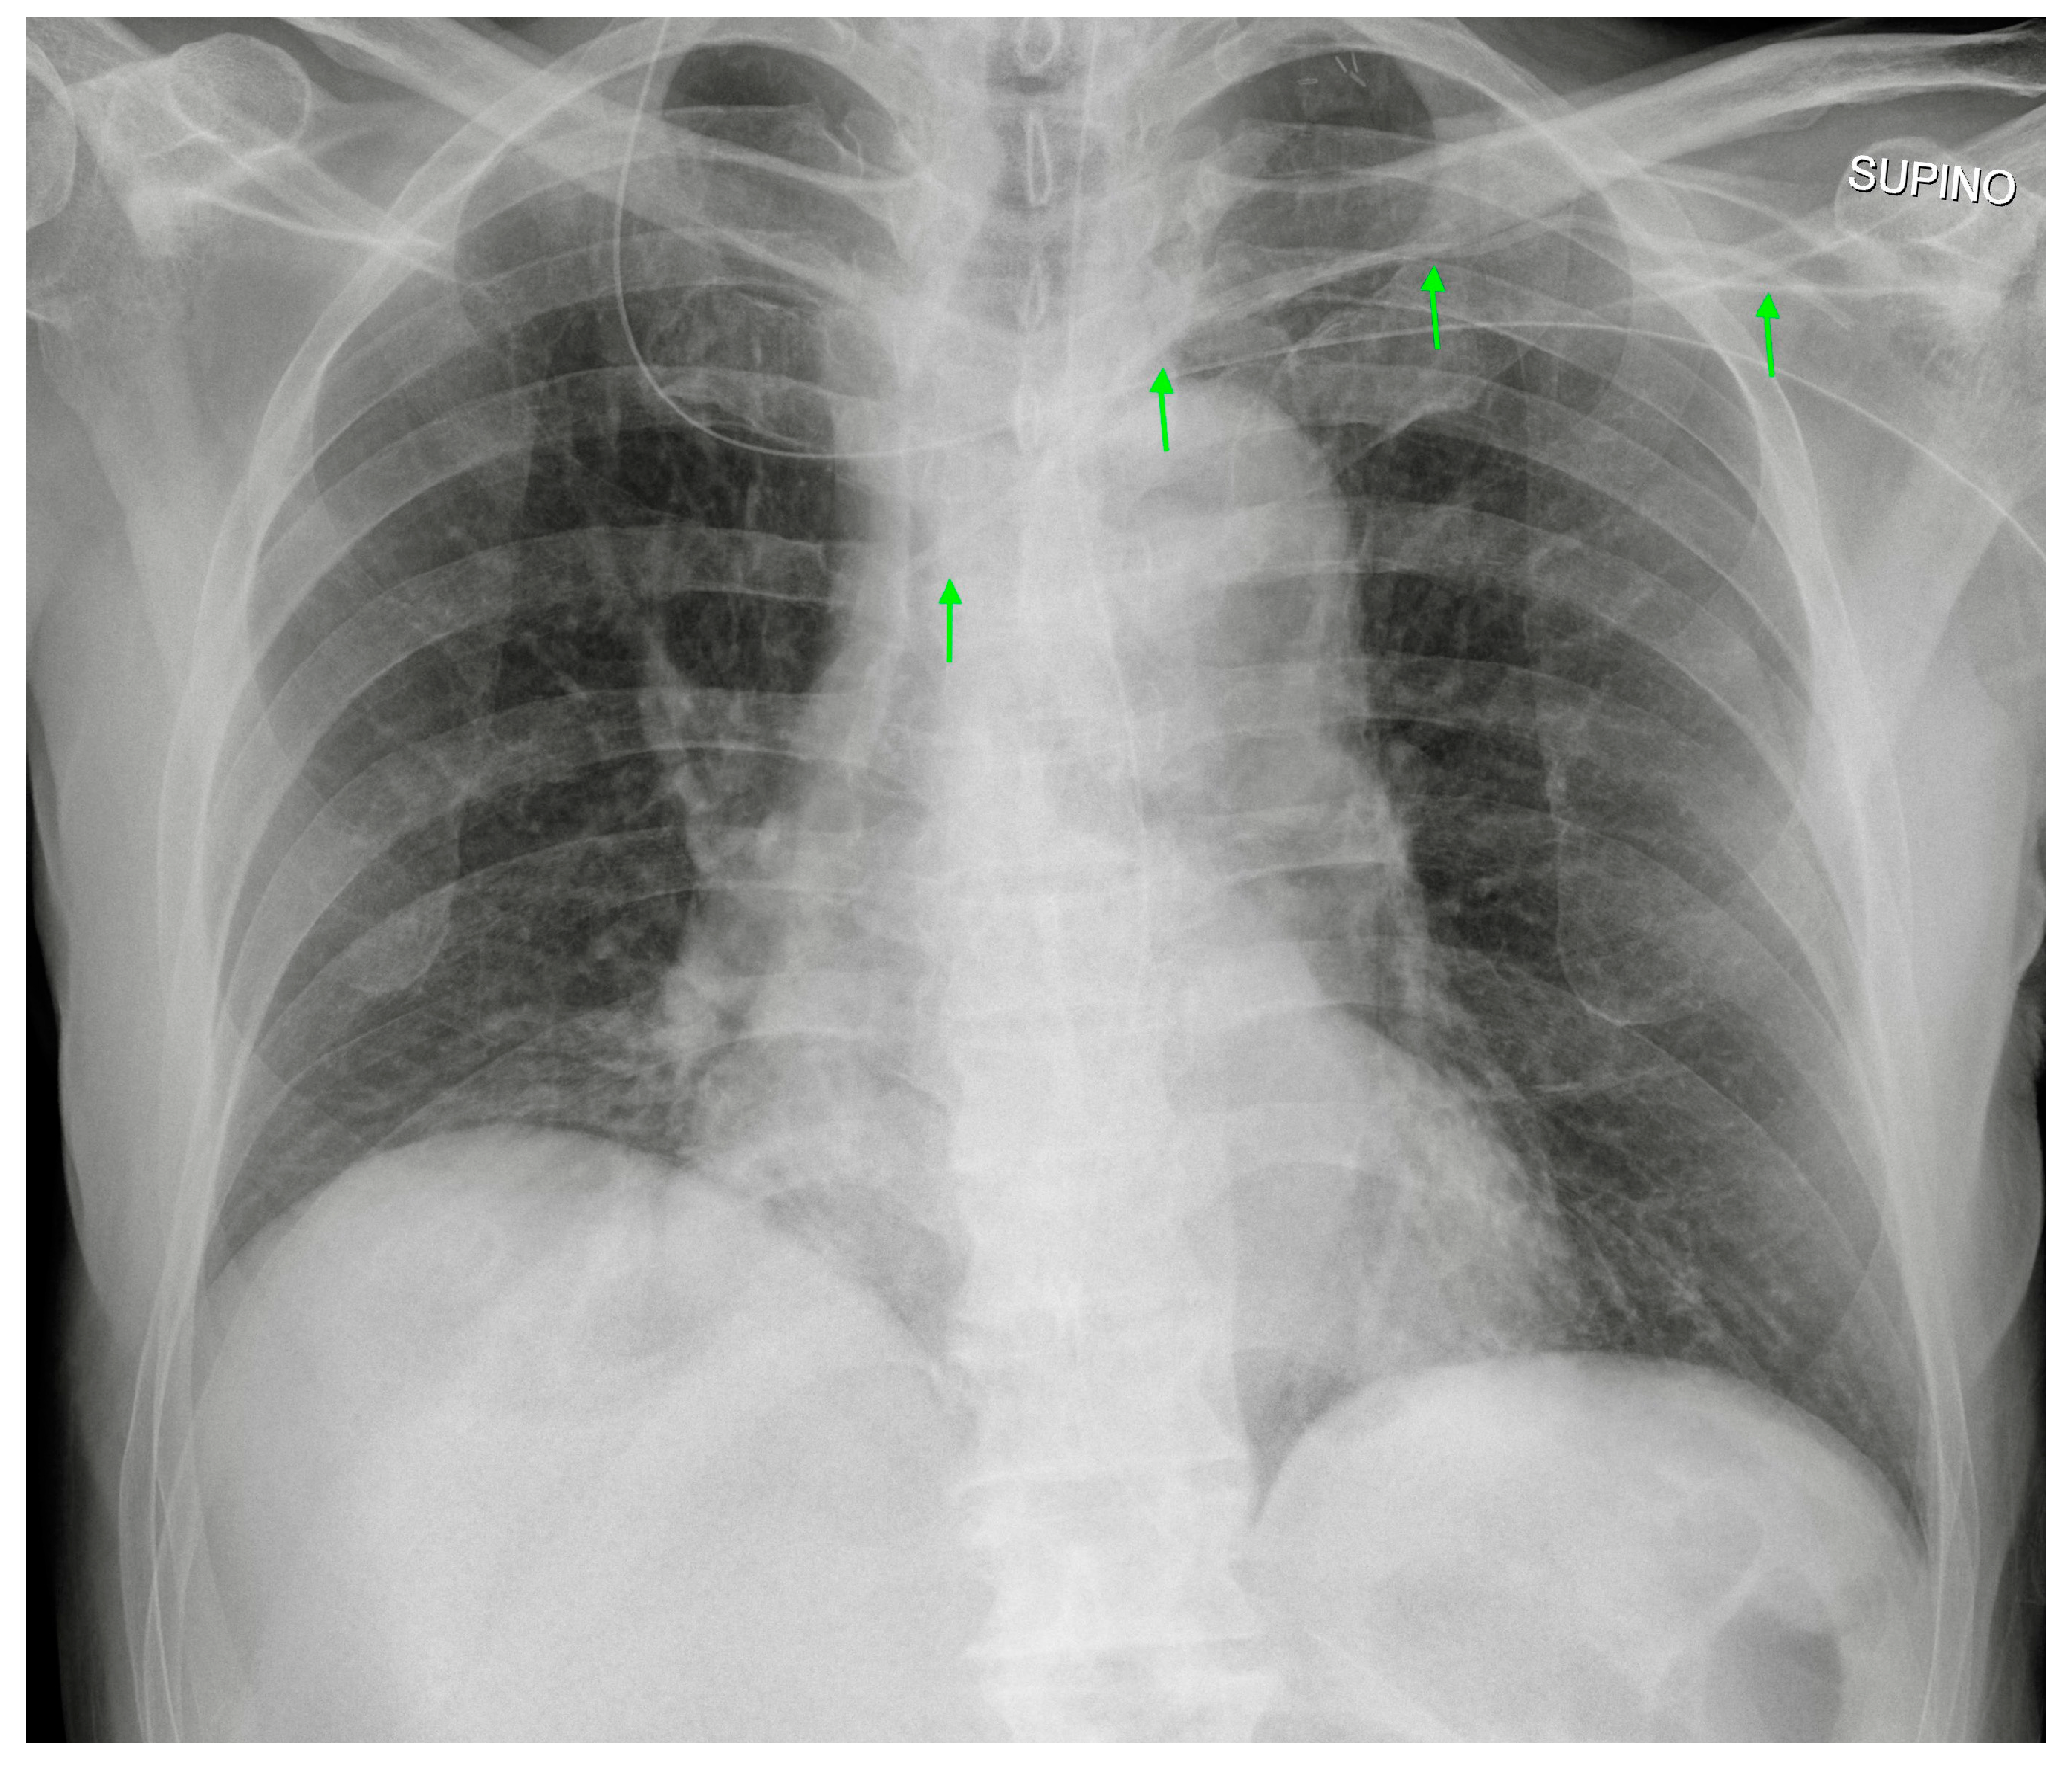

Figure 6.

Left-inserted PICC with tip inside the SVC (green arrows).